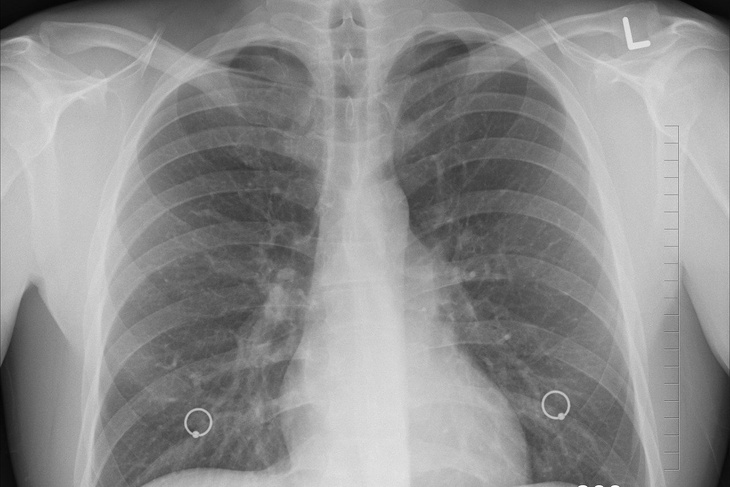

Врач-инфекционист Первого Санкт-Петербургского медицинского университета имени Павлова Оксана Станевич сообщила об увеличении числа пациентов с COVID-19, у которых происходят спонтанные «разрывы легких».

По ее словам, разрывы чаще всего происходят в наиболее воспаленной области легкого. Но порой достаточно даже небольшого числа участков «матового стекла».

«При этом осложнении воздух скапливается между листками плевры, наступает коллабирование легкого, оно спадается и нарастает дыхательная недостаточность. Это уже острая хирургическая ситуация, необходимо дренировать легкое, выпускать воздух», — пояснила Станевич в разговоре с «Лентой.ру».